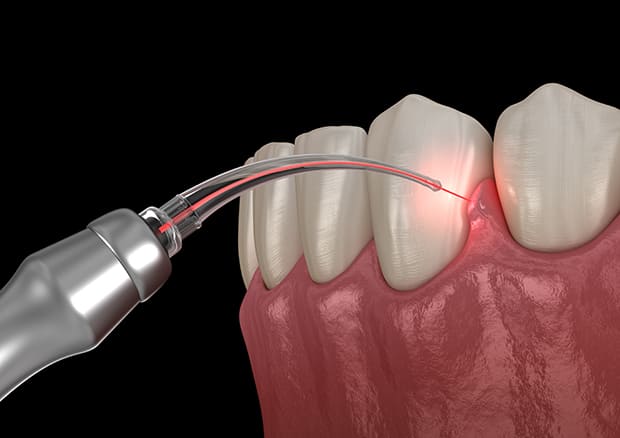

歯周病菌を光殺菌するPDT療法

従来とは全く異なった新しい概念の歯周病治療法が、PDT(Photo Dynamic Therapy=フォトダイナミックセラピー)と言われる「光線力学療法」です。

PDTは医科でもがん治療やニキビ治療などに有効で積極的に取り入れられています。

光によって活性化するバイオジェル(光活性剤)を歯周ポケットに注入し、ここに「ペリオウェイブ」と呼ばれるレーザーを照射させます。レーザー照射により、バイオジェルが化学反応を起こすことで、活性酸素が生成され、患部の殺菌が実現します。

PDTは殺菌効果が強いため歯周病治療に有効とされています。